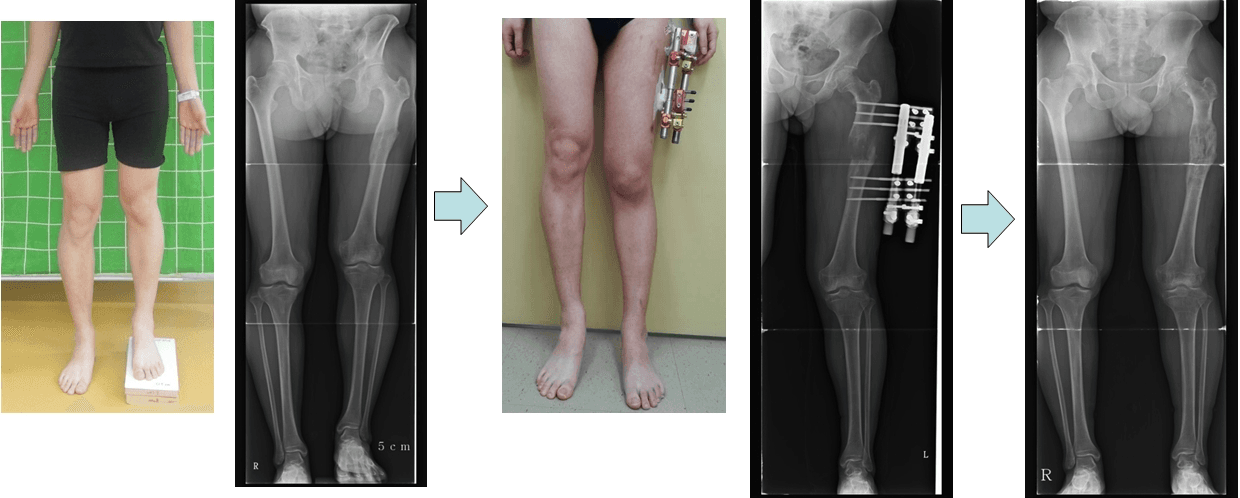

This is a patient whose femur on one leg was shorter than the other. This shows the length of both legs being equal after surgery.